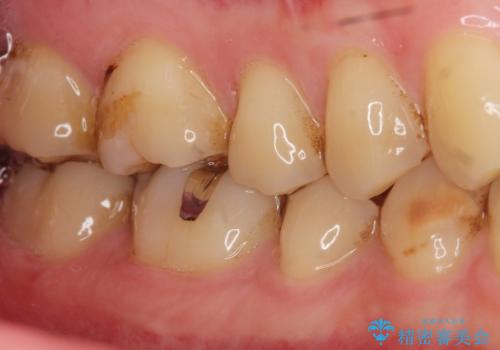

- 奥歯に食べ物がはさまることを主訴に来院された患者様です。

精査したところ、神経近くに及ぶ大きなう蝕を認めました。

神経をとらずに済むよう丁寧にう蝕を除去したのち、セラミックインレーで修復しました。